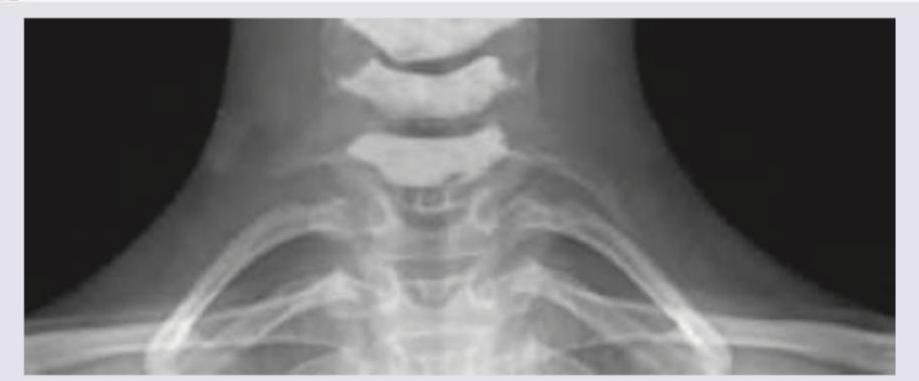

Question 3: A 25-year-old female presents with neck pain and tingling sensation in her left arm. An X-ray of the cervicothoracic region is obtained. What is the radiological finding shown in the image?

- A. Cervical rib (Correct Answer)

Explanation: ***Cervical rib*** - The image displays an extra rib arising from the **C7 cervical vertebra**, which is characteristic of a cervical rib. - This **supernumerary rib** extends towards the sternum or first thoracic rib, a classic radiological finding. *Costochondritis* - **Costochondritis** is an inflammation of the cartilage connecting the ribs to the sternum, which is typically a clinical diagnosis, not visible on X-ray. - An X-ray would not show inflammatory changes in cartilage or soft tissue, making this diagnosis unlikely based on imaging alone. *Fracture of 2nd rib* - A **fracture of the 2nd rib** would appear as a discontinuity or break in the normal bony architecture of the second rib. - The image does not show any signs of a broken rib; instead, it shows an **extra, well-formed rib-like structure** originating from the cervical spine. *Spondylolisthesis* - **Spondylolisthesis** involves the anterior displacement of one vertebral body over another, usually in the lumbar spine. - This condition is also not visible in the provided image, which focuses on the cervicothoracic junction and shows an **anatomic variation** rather than vertebral slippage.